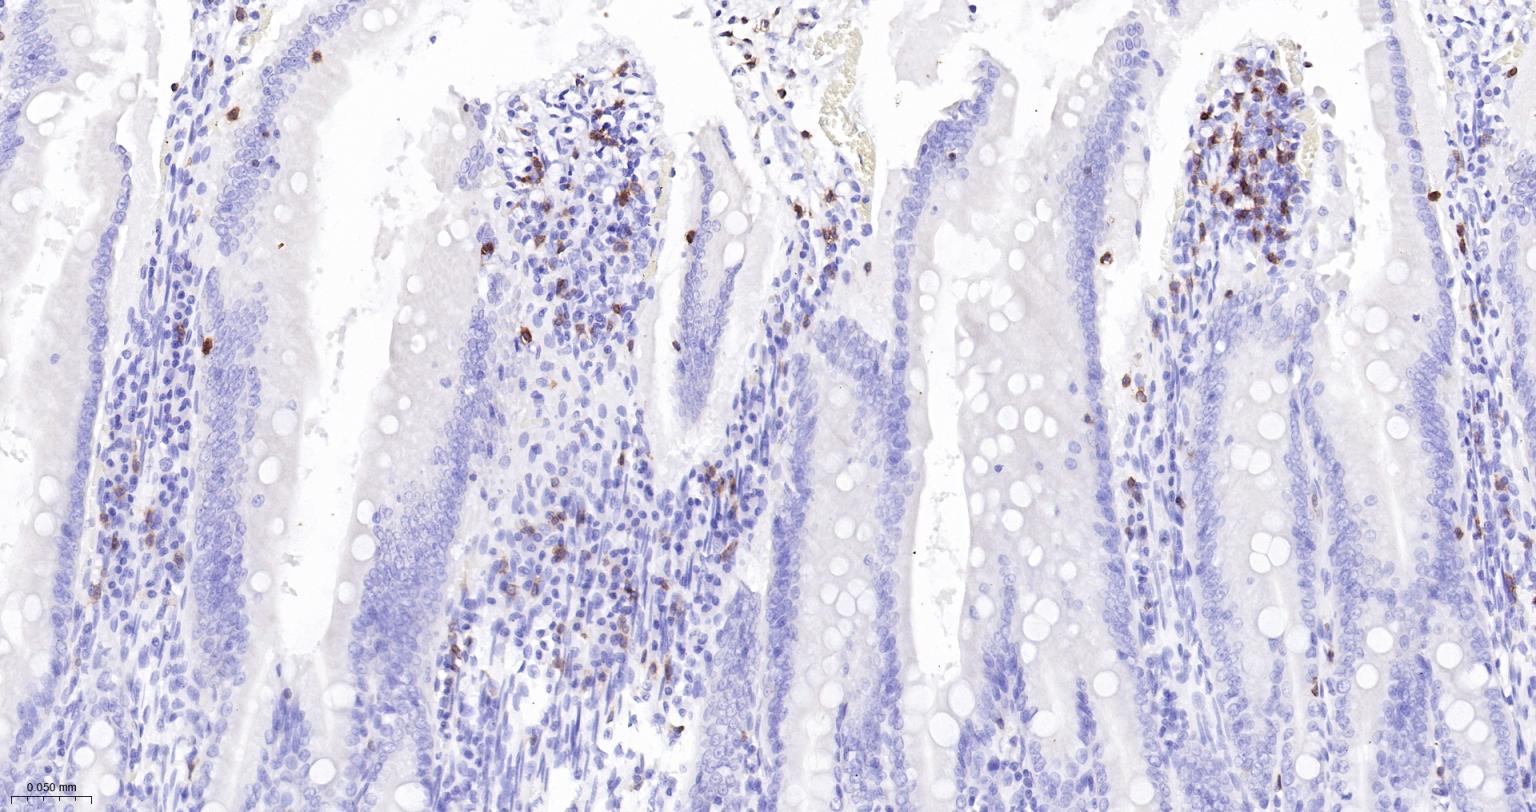

Paraformaldehyde-fixed, paraffin embedded Human Small Intestine; Antigen retrieval by boiling in sodium citrate buffer (pH6.0) for 15 min; The section was incubated with CD3E Monoclonal Antibody, Unconjugated (bsm-54036M) at 1:200 overnight at 4°C, followed by conjugation to the bs-40296G-HRP and DAB (C-0010) staining.